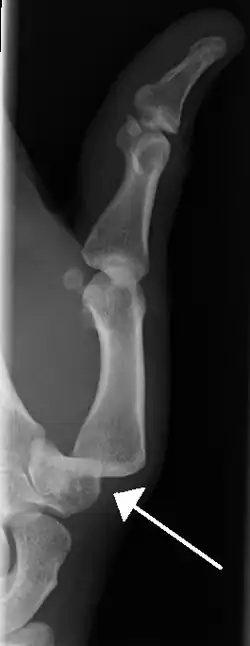

Dislocation of the carpo-metacarpal joint.